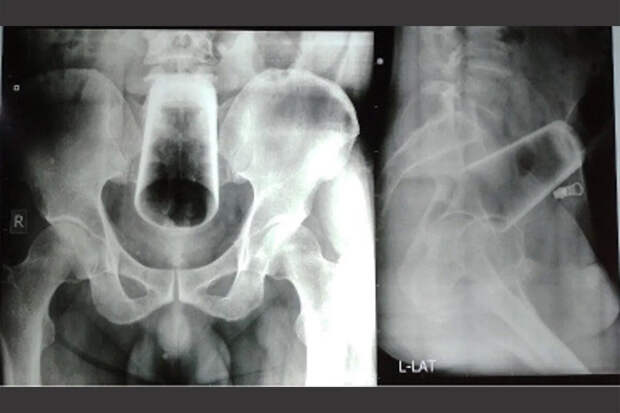

Житель Непала попал в больницу с застрявшей в заднем проходе бутылкой, пишет Independent.

Мужчина рассказал врачам, что произошедшее - несчастный случай. Сначала он сам пытался достать инородное тело, но только лишь усугубил ситуацию. По словам медиков, пациенту повезло, что стекло не лопнуло - это могло бы привести к сильному кровотечению и серьезным травмам.

Хирургам пришлось делать мужчине срочную операцию, которая закончилась благополучно. Мужчина неделю пролежал в больнице, а через два месяца после процедуры полностью выздоровел. Сообщается, что у нет каких-либо психических заболеваний.